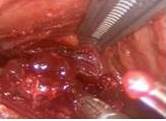

Se reseca la glándula y se extrae la pieza operatoria (Figura 7). El corte congelado en los tres casos reportó negativo para malignidad. Se hace hemostasia y se tiene especial cuidado por la ubicación inferior de la vena yugular interna (Figura 9).

Finalmente, colocamos Gelfoam® en el lecho quirúrgico (Figura10) y drenaje cerrado aspirativo.